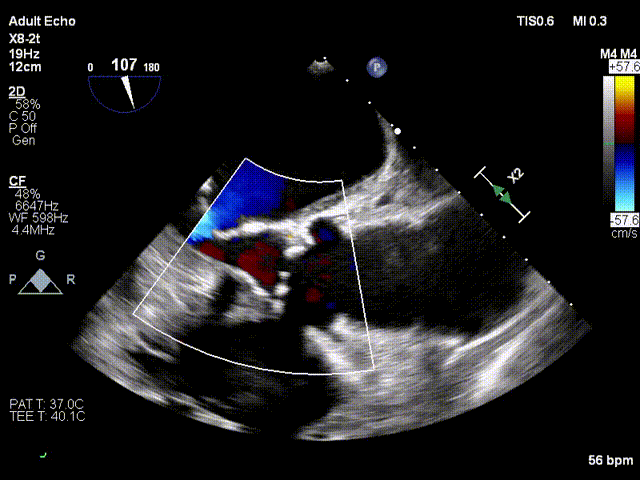

三、超声评估

超声心动图显示患者重度主动脉瓣狭窄伴中度关闭不全,Vmax 5m/s, PG mean 59mmHg,PG max 102mmHg;室间隔16mm,左室后壁13mm;LVDd=40mm,LVDs=26mm;LVEF=62%。

术中超声评价:跨瓣流速1.6m/s,平均跨瓣压差5mmHg,可见少量瓣周漏。